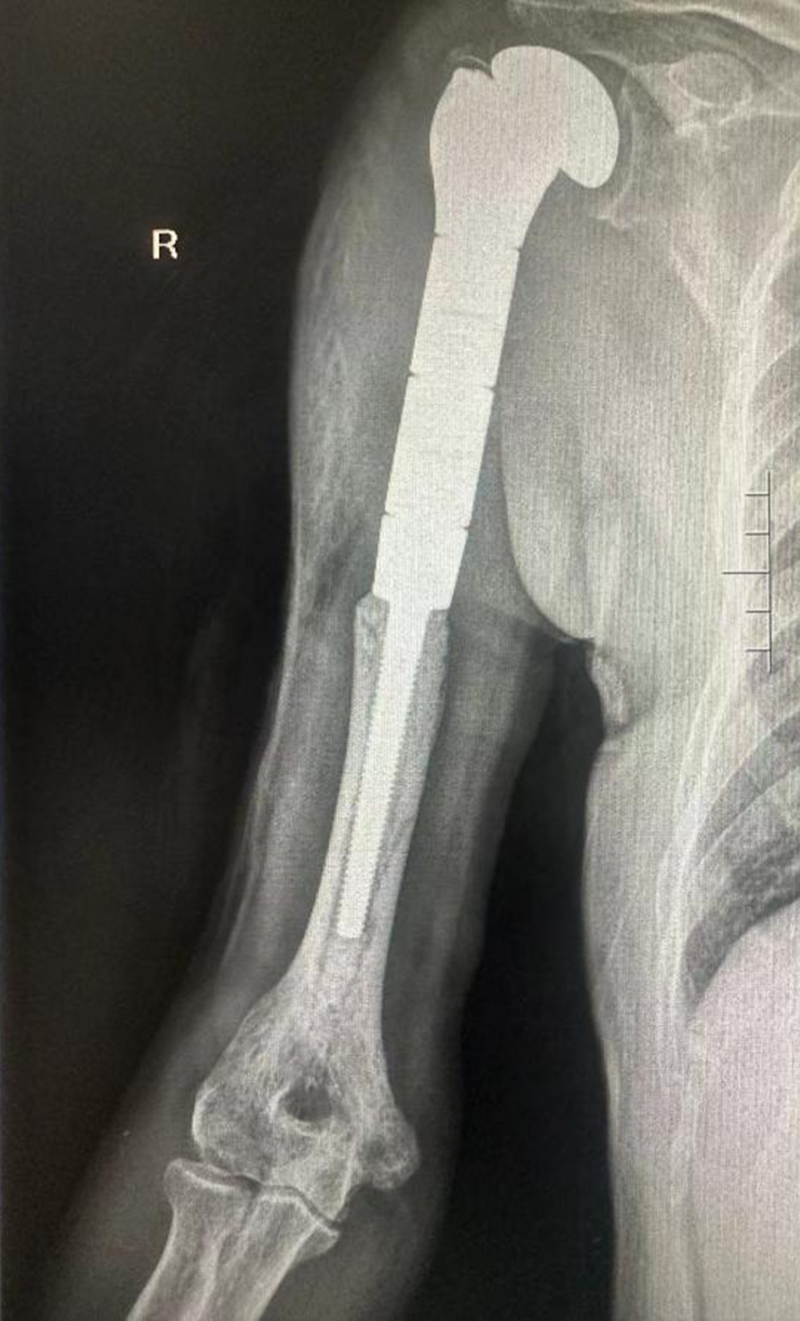

患者小王,17岁,因右大腿肿痛10个月不能行走,确诊为“右大腿股骨骨肉瘤”。入院后,骨科主任、关节外科病区主任、主任医师吴军团队结合患者肢体“病变范围发展快、范围大,靠近膝关节”的特点,为其制定了“先放化疗,再手术,再规范化疗”的治疗方案,在肿瘤科协作下,患者完成放化疗疗程后转骨科关节外科病区手术。放化疗后,尽管小王肿瘤有缩小,但肿瘤仍然侵及整个股骨下端、股骨髁和股中间肌,关节结构破坏严重。经过反复比对、测量,并利用电脑模拟切除肿瘤后关节重建范围等术前准备,吴军团队凭借娴熟和丰富的综合骨科经验,在完整保留股内外侧肌、股直肌、股骨近端、胫骨平台和神经血管的基础上,完整切除波及股骨及关节的肿瘤,按术前规划成功实施了股骨下段和膝关节的假体置换和重建。

术前,化疗后

小王爸爸高兴地说:“州医院骨科的治疗和手术远远超过预期,我们看到了新的希望!非常感谢!”术后,在关节外科医护团队的细致治疗和护理下,小王已经能够自由行走,准备进行下一步治疗。

手术完美重建股骨、膝关节